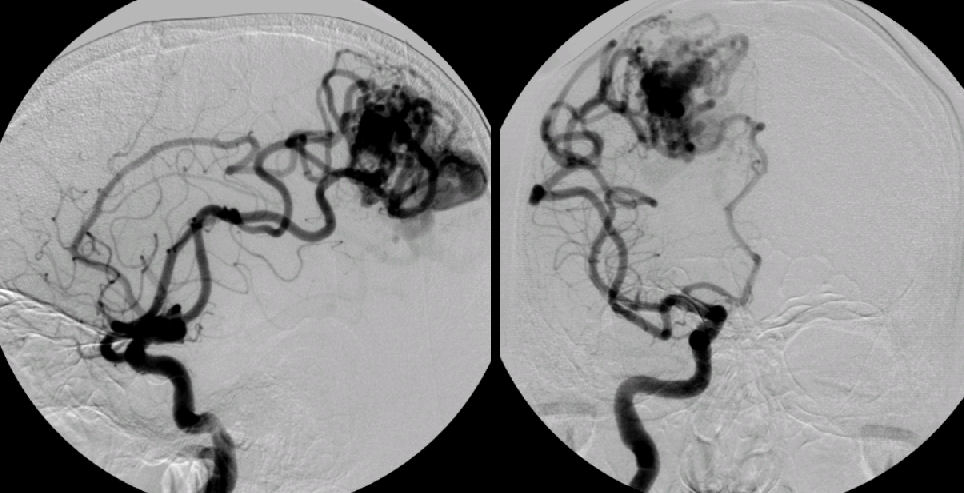

Хирургические процессы при эмболизации гемангиомы на фото

Раздел: Снимки-откровения